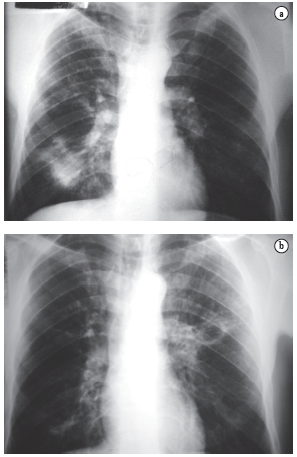

Of the 227 patients, 36 (15.8%) reported having been previously treated for TB. However, only 18 (7.9%) presented positive sputum smear microscopy for acid-fast bacilli or positive sputum culture for Mycobacterium tuberculosis. Of those 18 patients, 17 were Caucasian males, presenting a mean age at the time of diagnosis of 43.3 years (range, 30-56 years). The remaining 18 patients, all of whom were Caucasian males, presented a mean age at the time of diagnosis of 49 years (range, 35-69 years), presented negative results, and did not present clinical improvement after the anti-TB treatment had been started. However, all 18 responded to the anti-PCM treatment (Figure 1).

In most cases, the clinical complaints, the physical examination data, and the radiological alterations presented by these patients did not allow a clear distinction to be made between the two diseases in most cases (Figures 2-4).